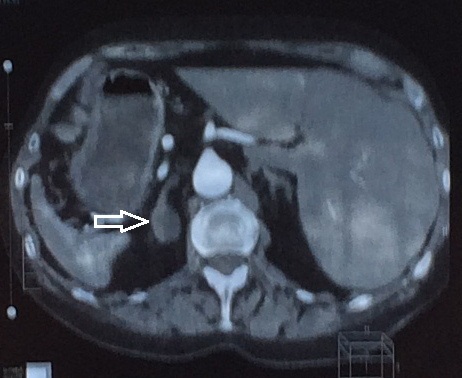

1. МСКТ брюшной полости и забрюшинного пространства | |

| Тема | ||

| Тип | Исследовательские инструменты | |